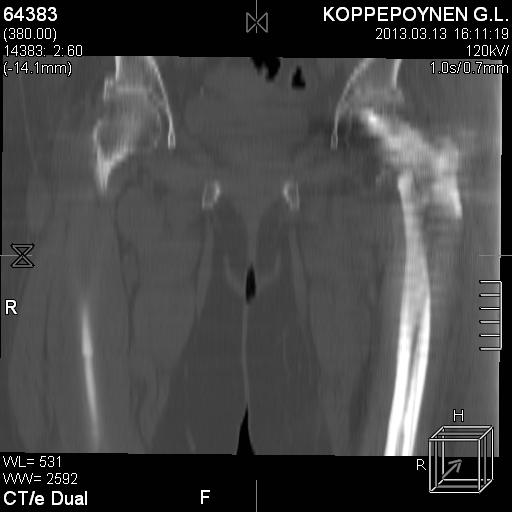

[Ortho] Чрезподвертельный перелом бедра. Остеосинтез стержнем. Перелом металлофиксатора. Дальнейшая тактика?

Делали КТ после операции.